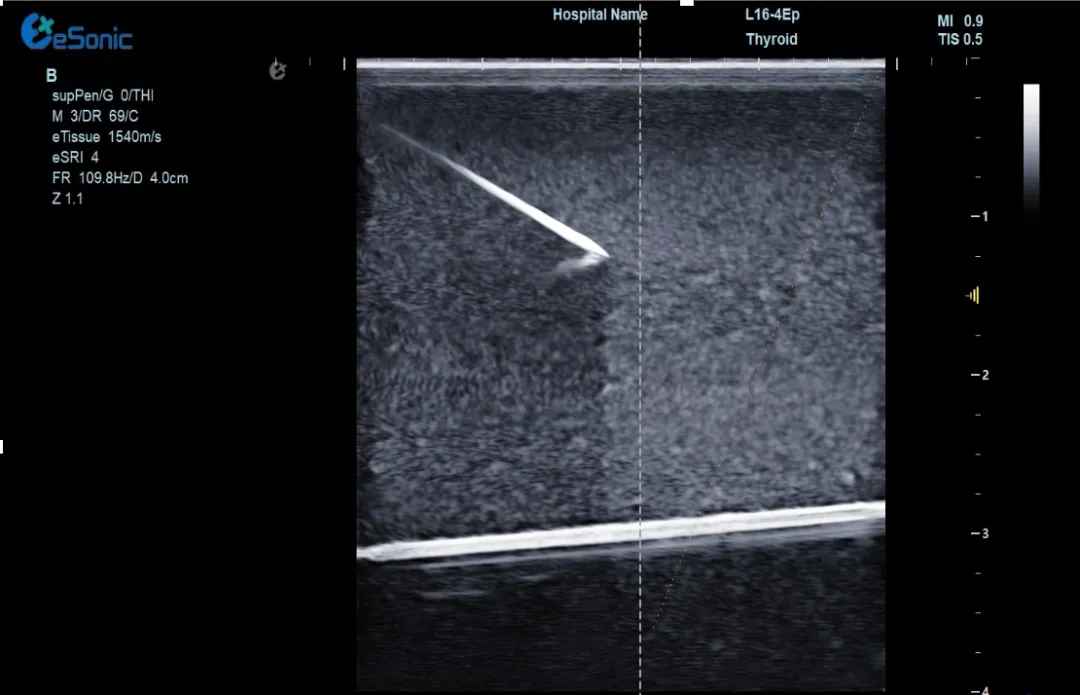

治疗当天,超声介入科董刚教授将一根细细的消融针穿刺到甲状腺结节内,通过针尖产生热量,高温加热作用可以使结节病灶组织被精准灭活,最后坏死组织随着时间的推移逐渐被身体吸收,直至消失。

640 (3) (2).gif

(甲状腺结节射频消融动态视频)

李女士接受了甲状腺射频消融手术,过程顺利,手术耗时约20分钟,患者无出血、声音嘶哑等并发症。术后生命体征正常,观察几小时后便回家休息。次日恢复正常生活,颈部几乎看不到明显伤口。复查时显示甲状腺结节缩小,吞咽异物感消失。术后李女士摸着几乎无痕的颈部笑到:“没想到20分钟就解决了困扰我几年的问题!为微创射频消融技术点赞!”